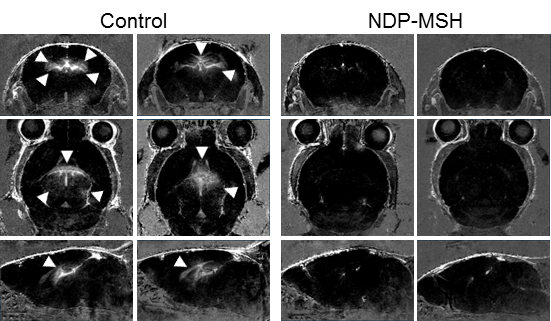

NDP-MSH inhibits the progression of ongoing EAE. MRI of brains from NDPMSH–treated mice and controls at disease maximum. Two representative images of a multiplanar reconstruction per group are shown. Signal enhancement in the brain due to contrast agent accumulation is marked by white arrows. - © C. Faber / K. Loser Dieses zentrale Projekt bietet dem SFB alle erforderlichen Geräte, Methoden und Protokolle für: